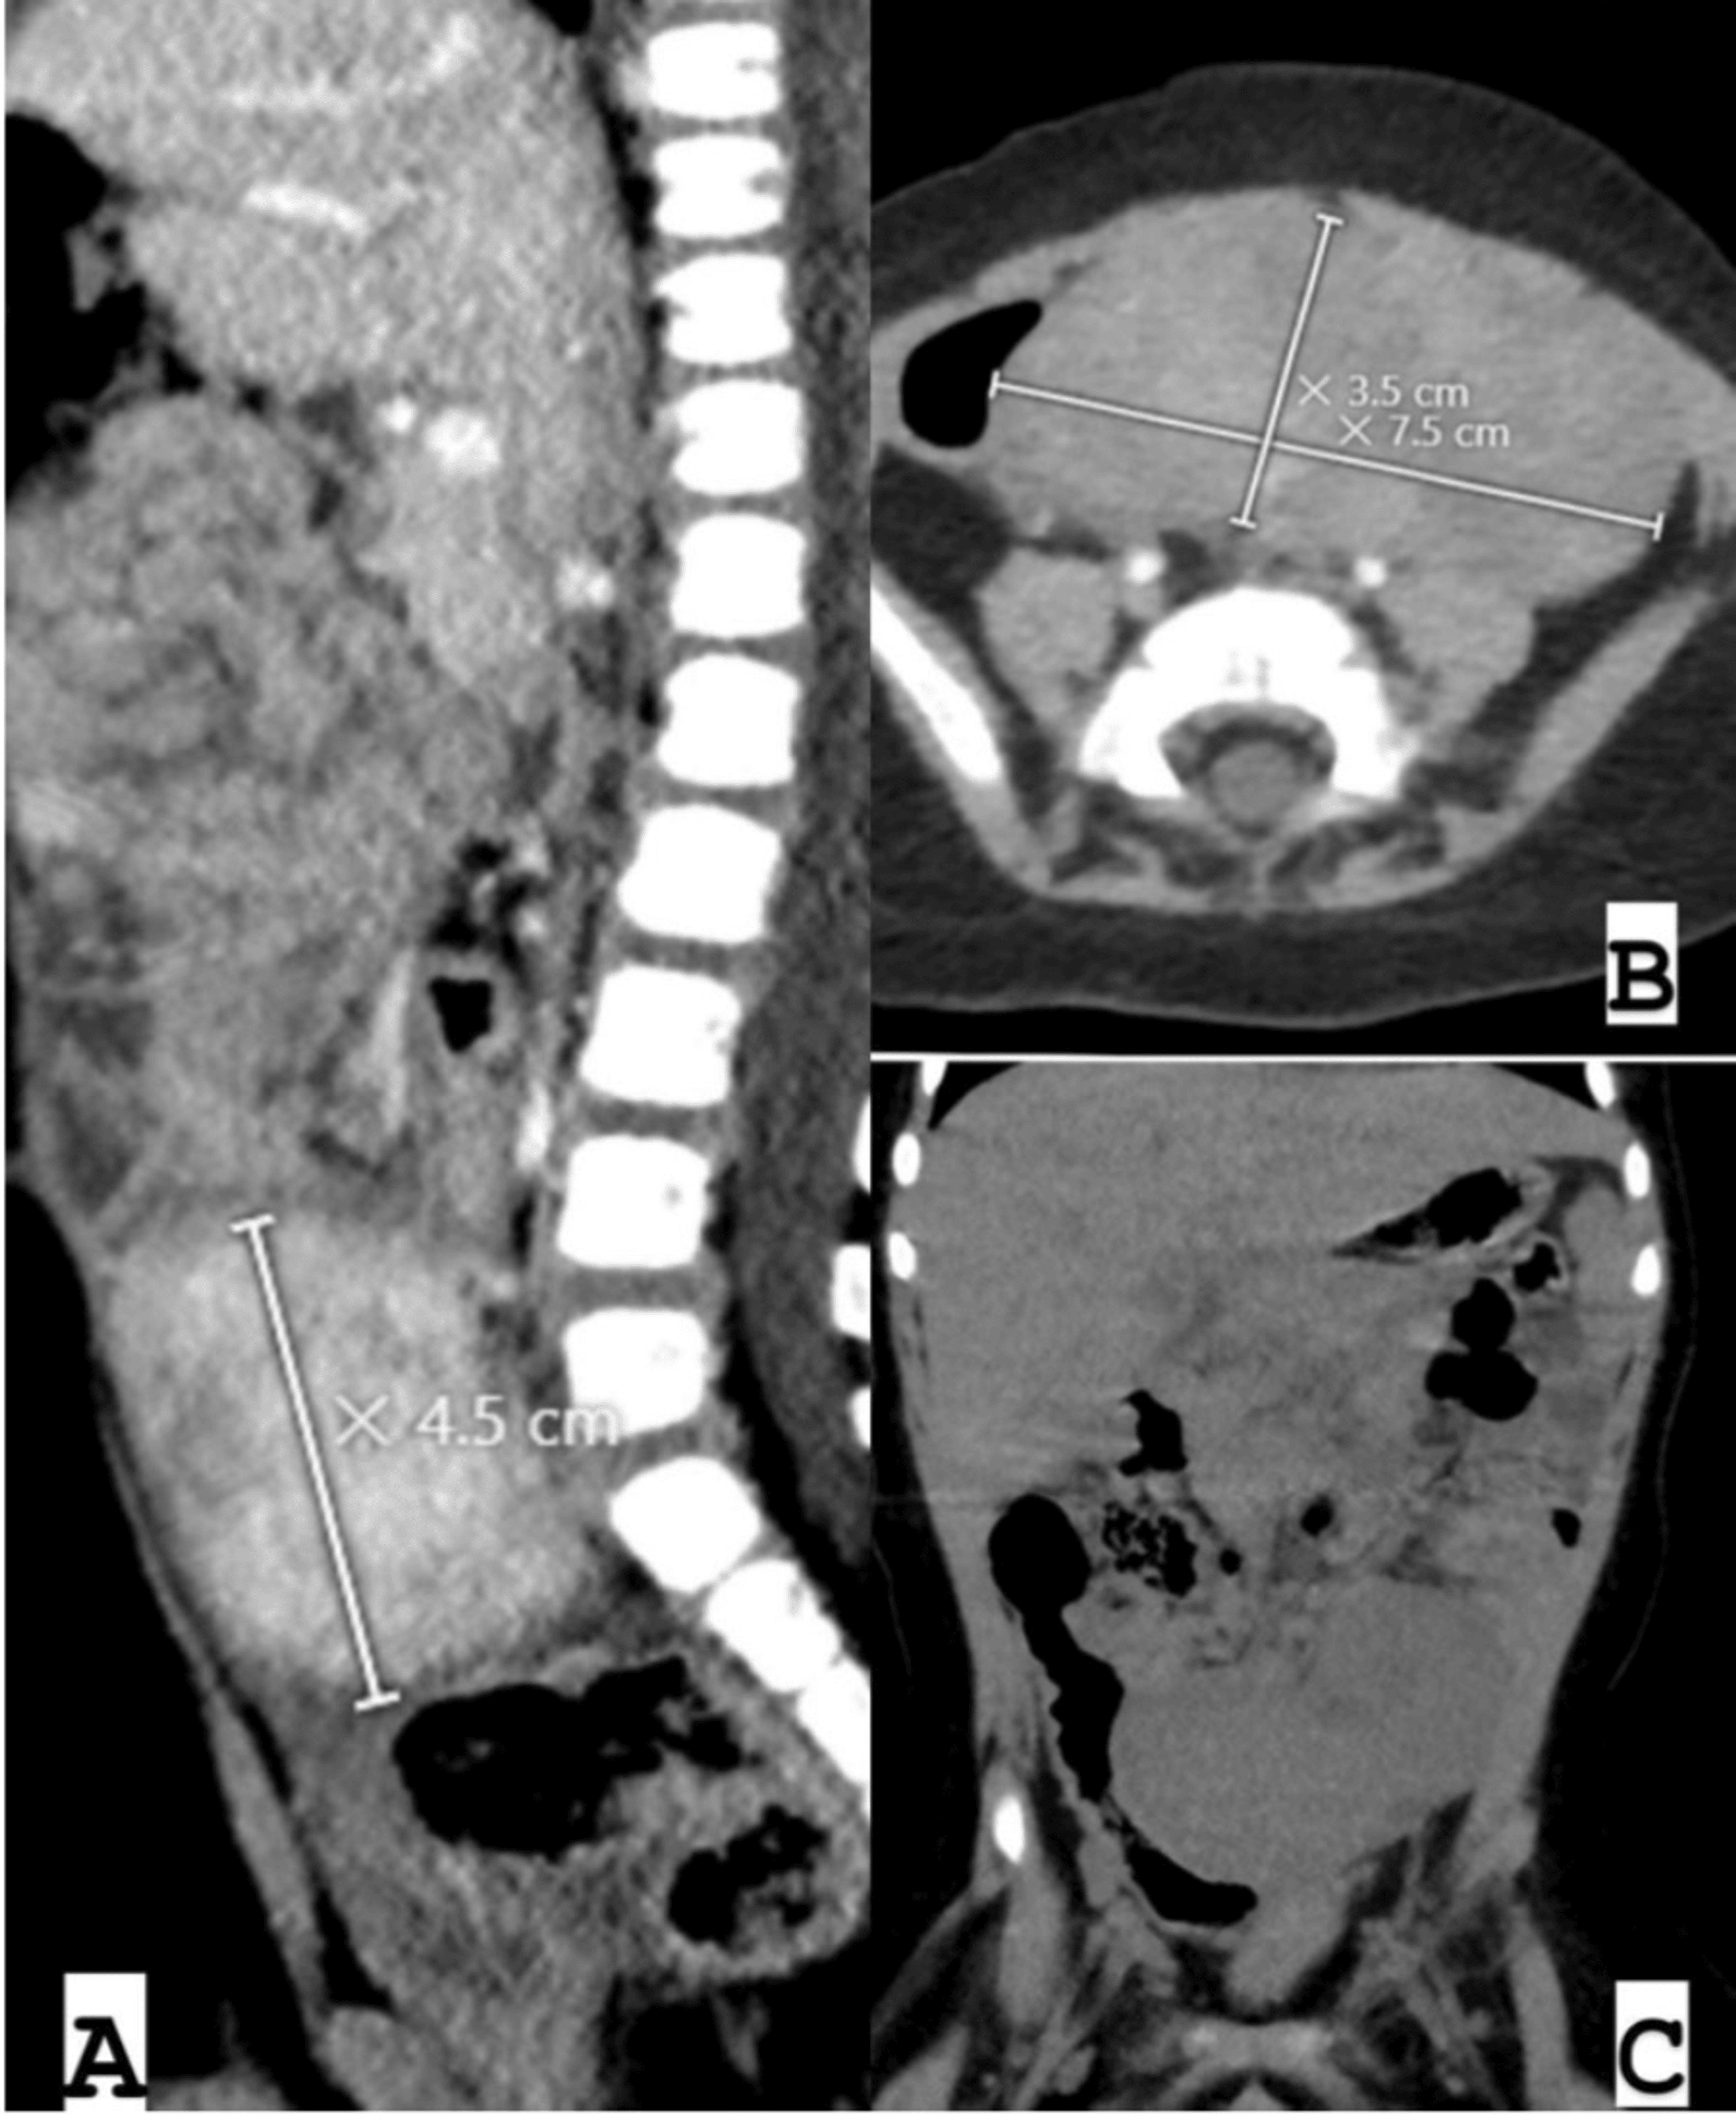

Subsequent ultrasound scans yielded similar results, leading to an abdominal CT scan, which confirmed a large pelvic mass measuring 7.5 × 3.5 × 4.5 cm, consistent with a neurogenic tumor (Figure 1). The abdominal CT scan demonstrated a well-defined, bilobed, heterogeneously enhancing mass lesion with surrounding inflammatory changes and free fluid. The location of the mass in proximity to the paramidline lower abdomen, anterior to the iliac vessels, and its displacement of adjacent bowel loops raised suspicion for a neurogenic tumor. These characteristics, including the heterogeneous enhancement and lack of significant calcifications, aligned with features commonly associated with neurogenic tumors in pediatric patients.

During surgery, the laparotomy revealed an encapsulated mass measuring approximately 7.5 × 3.5 × 4.5 cm, located in the mid-abdomen and originating from the mesentery about 10 cm proximal to the terminal ileum (Figure 2). The mass extended along the mesentery but was distinct from the bowel lumen and displayed a firm to hard consistency. It was successfully enucleated from the mesentery while preserving adjacent structures. The terminal ileum appeared dusky due to compression of mesenteric vessels by the tumor, necessitating a 10 cm resection of the affected bowel segment with primary anastomosis. The appendix exhibited inflammation at its mid and distal tip, justifying an appendectomy. No significant ascites was observed. Multiple enlarged mesenteric lymph nodes surrounding the tumor were noted and biopsied.